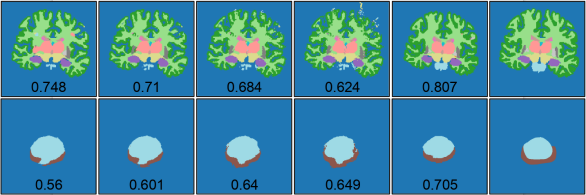

iii. Lastly, we asked the question: Is test-time adaptation required at all, or can the accuracy on TDs be improved by simply passing the predicted segmentation multiple times through the DAE? The results of this experiment are shown in last two rows of Table 2 and in Fig. 4, for different number of passes through the DAE. We observed that such a post-processing approach could not improve segmentation accuracy as much as the test-time adaptation. On the contrary, for the brain datasets, where the segmentations are more complicated than other anatomies due to the presence of multiple structures, the post-processing with multiple DAE passes worsened the segmentation accuracy. We believe that this might be because the DAE output, although generally plausible according the labels in the SD dataset, is not necessarily tied to the input image in question. The proposed method constrains the predicted segmentations to be tied to the input image by: (1) freezing the NI2S CNN and (2) keeping the adaptable I2NI CNN relatively shallow. Also, the limited flexibility for the adaptation guards against potential errors of the DAE such as the one seen fourth column for the brain dataset in Fig. 4.